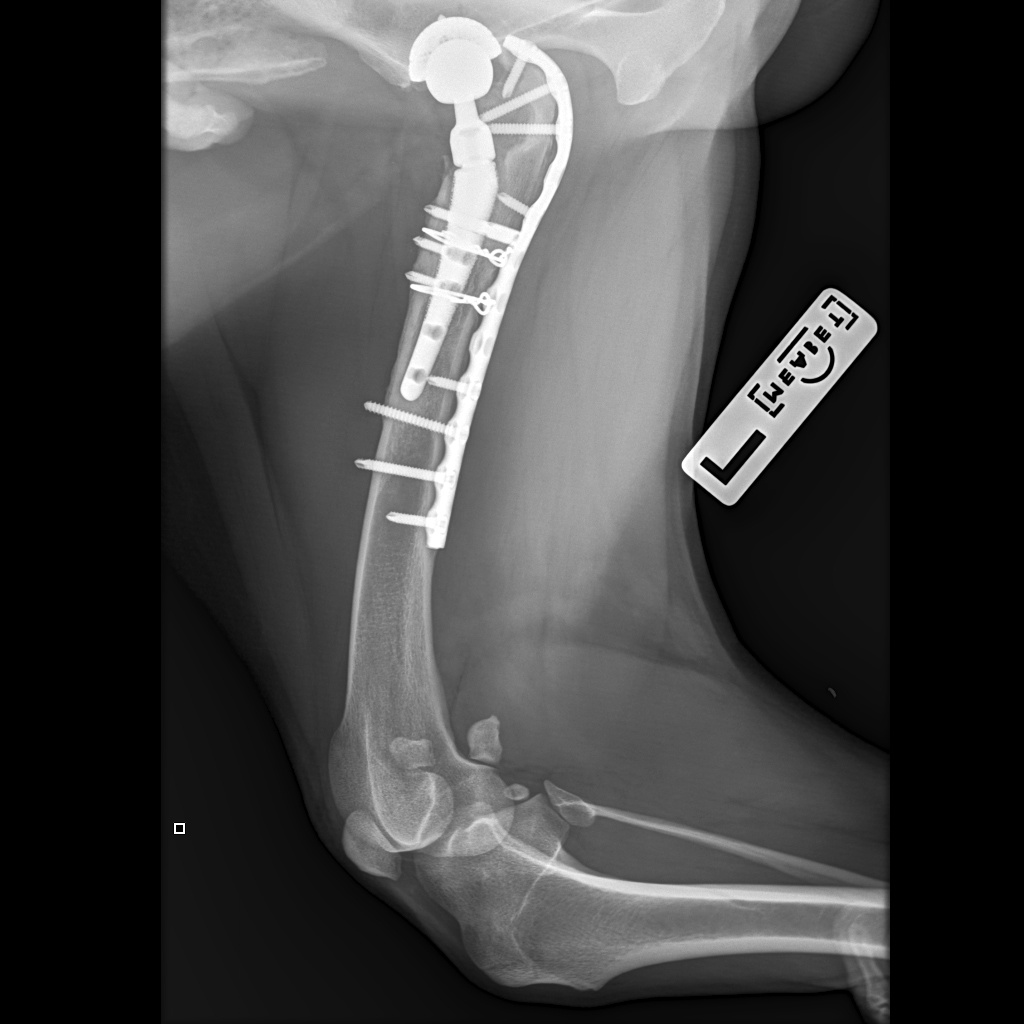

19.05.2023

Вчера резко захромал, встал на 3 ноги и понос.

По рентгену чисто

В понедельник КТ